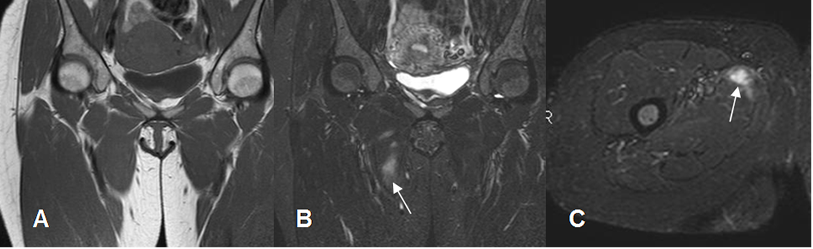

Fig 20. Distensión muscular grado 1.

A: RM coronal en T1. Grupos musculares sin alteraciones.

B: RM coronal y C: RM axial en STIR. Lesión hiperintensa en el músculo aductor mediano, por distensión muscular grado I.